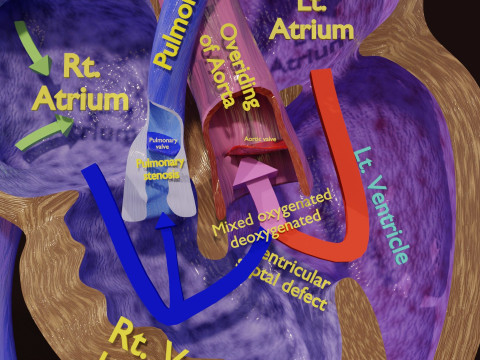

The model meshes include adult circulation versus circulation in Tetralogy of Fallot (TAF), arrow labels and text labels. The blood flow in a patient with Tetralogy of Fallot is outlined in this model. To contrast it to normal blood circulation a separate model of normal circulation is included. The Tetralogy of Fallot (OVER RIDING OF AORTA, PUL STENOSIS, VENTRICULAR SEPTAL DEFECT, RIGHT VENTRICULAR HYPERTROPHY), fossa, ligament teres , venosus, and arteriosus are duly depicted with proper labelling and blood flow directional arrows. Excellent model for teaching, demonstration and knowlegde of human body. The models include both procedural and image textures blend files separately. The texture file include diffuse, roughness and normal png and jpeg based on non overlapping UV maps.